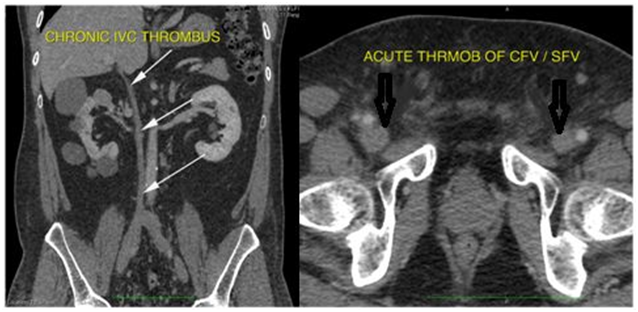

CT Abdomen with contrast showed right kidney 10X6.1cm with >10cysts, Left kidney 9.6X5.1cm with 3-4 cysts, the largest cyst on either side measuring about 6cm (Figure 2). Tc-99m Isotope renogram scan revealed total GFR 65ml/min (left kidney 52ml/min, right kidney 13ml/min).

Figure 2 CT Abdomen with contrast shows Right kidney 10X6.1cm with >10cysts, Left kidney 9.6X5.1cm with 3-4 cysts, the largest cyst on either side measuring about 6cm with Tc-99m Isotope renogram revealed total GFR 65ml/min(left kidney 52ml/min, right kidney 13ml/min).